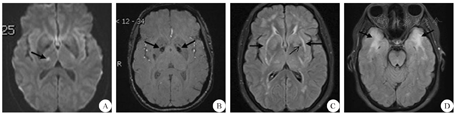

患者 女,42岁,因"左颜面部、左手麻木7 d"于2017年10月8日收治于我科。患者2016年开始出现反复头痛、精神抑郁、睡眠差、记忆力减退。否认高血压、糖尿病及烟酒嗜好。父亲有脑梗死病史。体检左面部针刺觉过敏。实验室检查结果提示:乙肝表面抗原、e抗体、核心抗体均阳性,乙型肝炎病毒-DNA定量1.91×104 IU/mL;抗核抗体-核颗粒型1∶100。头颅MRI示右侧丘脑急性期腔梗,脑白质多发异常信号,左侧基底节区、放射冠扩张血管间隙,双侧基底节区局灶性铁沉积(图1)。心电图、心脏B超、颈部血管B超、经颅多普勒超声均未见明显异常。拟做基因检测,未获同意。诊断:急性脑梗死(小动脉闭塞型),予抗血小板聚集、调脂稳斑、营养神经、改善循环等治疗后好转出院。

A:DWI上可见右侧丘脑新发梗死(箭头所示);B:SWI上可见双侧基底节区局灶性铁沉积(箭头所示);C:FLAIR上可见脑白质多发异常对称性高信号,累及外囊(粗箭头所示);左侧基底节区可见扩张血管间隙(细箭头所示);D:FLAIR上可见脑白质多发异常,累及双侧前颞叶(箭头所示);DWI:扩散加权成像;SWI:磁敏感加权成像;FLAIR:液体衰减反转恢复序列